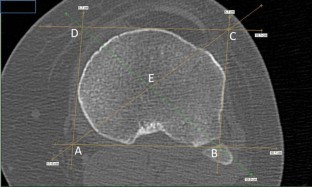

The angle formed from the tibial geometric centre to the intersection of both lines from the middle of the tibial tuberosity and its medial border was measured in 50 patients. The geometric centre was determined on an axial CT slice at 10 mm below the lateral tibial plateau and transposed to a slice at the level of the most prominent part of the tibial tuberosity. Similar measurements were taken in 25 patients after TKA, in order to simulate the intraoperative appearance of the tibia after making its proximal resection.

This study found that in 90 % of the patients, the medial border of the tibial tuberosity is internally rotated 17°–24° in relation to the line connecting the middle of the tuberosity to the tibial geometric centre. Since this anatomical landmark may be more easily identifiable intraoperatively than the commonly used “medial 1/3”, it can provide a better quantitative reference point and help surgeons achieve a more accurate tibial implant rotational position.